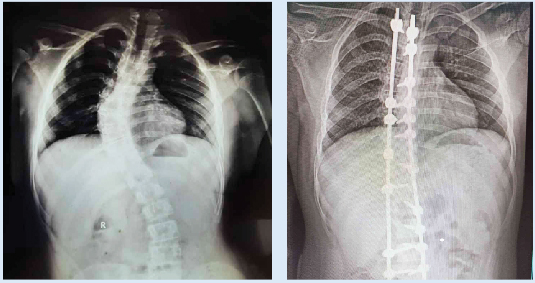

നട്ടെല്ല് ശസ്ത്രക്രിയക്ക് മുമ്പ്. 2. ശസ്ത്രക്രിയക്ക് ശേഷം

text_fieldsമുളങ്കുന്നത്തുകാവ്: ഗവ. മെഡിക്കൽ കോളജ് ആശുപത്രിയിൽ ആദ്യമായി നട്ടെല്ല് നിവർത്തുന്ന സ്കോളിയോസിസ് ശസ്ത്രക്രിയ നടത്തി. പതിമൂന്നുകാരനായ പാലക്കാട് കമ്മാന്ത്ര കിഴക്കേവീട്ടിൽ ഷൺമുഖത്തിെൻറ മകൻ ജിത്തുവിനാണ് സൗജന്യമായി സ്കോളിയോസിസ് എന്ന അതിസങ്കീർണ ശസ്ത്രക്രിയ ചെയ്തു നൽകിയത്. ശസ്ത്രക്രിയ ഒമ്പത് മണിക്കൂർ നീണ്ടു. നാലര അടി ഉയരമുള്ള കുട്ടിയായ ജിത്തുവിന് ജൻമനാ ഉണ്ടായതാണ് സ്കോളിയോസിസ്. സ്വകാര്യ ആശുപത്രികളിൽ ശരാശരി 10 ലക്ഷം രൂപ ചെലവുവരുന്ന ശസ്ത്രക്രിയ ദേശീയ ആരോഗ്യ മിഷന് കീഴിലുള്ള ആർ.എസ്.ബി.കെ പദ്ധതി വഴിയാണ് സൗജന്യമായി ചെയ്തത്.